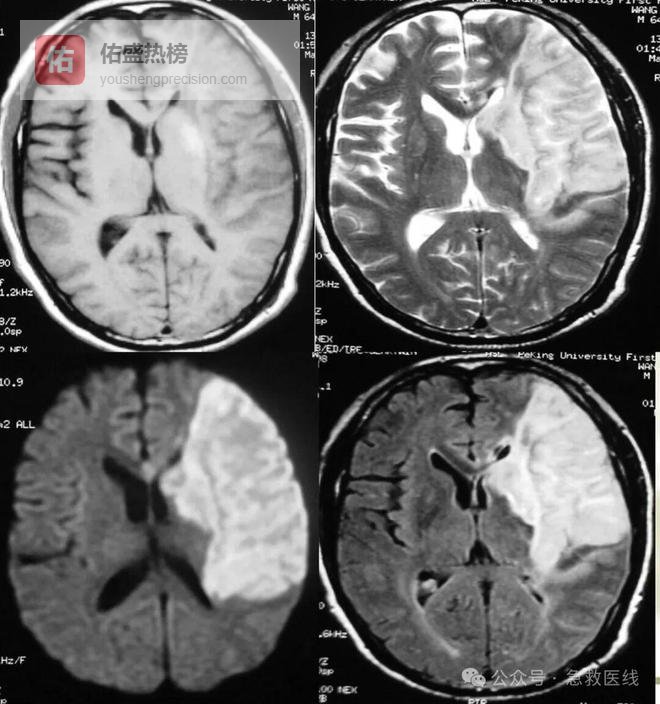

十二、脑梗死

(一)诊断

1、常于安静状态下发病;

2、大多数无明显头痛和呕吐;

3、发病可较缓慢,多逐渐进展,或呈阶段性进行

4、一般发病后1~2日内意识清楚或轻度障碍;

5、有颈内动脉系统和(或)椎-基底动脉系统症状和体征;

6、腰穿脑脊液一般不应含血;

7、头颅CT、MRI或脑管造影可明确诊断。